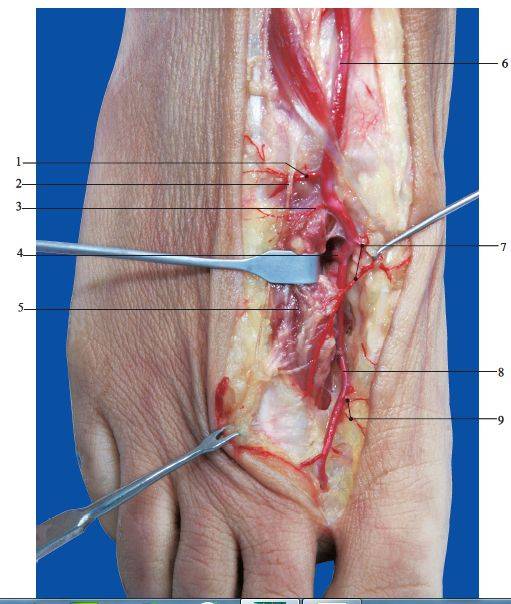

这是书中的部分解剖图片